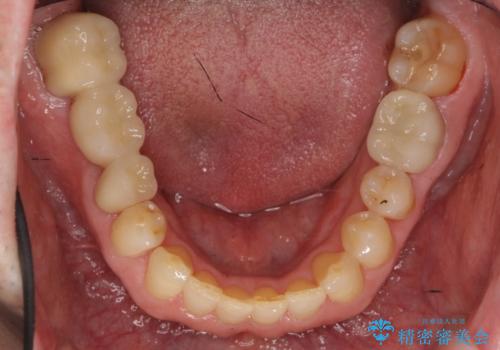

50代男性 受け口 他院で5年以上かかると治療を断られた

- 50代男性

- 受け口を主訴に来院。

他院での矯正相談は、5年以上かかると言われ、やんわりお断りされたとのことでした。

ずっと矯正はしたかったがあきらめていて、50代で退職を機に新しいことを初めて、歯並びも諦めずに治したいとのことでした。顎の手術は避け、歯の移動だけでの治療をご希望されていました。

ある程度時間はかかることは説明させていただき、治療開始しました。

矯正治療後、右下のインレーブリッジおよび左下の銀歯のやりかえを行なっています。

右上の八重歯は、右上の奥歯を矯正用ミニスクリューを用いて遠心移動を行い解消しました。

下の前歯はIPR(エナメル質を薄く削り歯を小さくする処置)を行なっています。